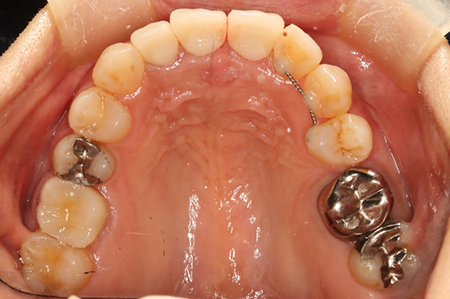

この患者様は長い事歯科医院には通っておらず、下の歯は前歯以外は全て崩壊していることが分かります。

前から見ても歯が欠けてしまい、歯茎も赤く腫れてしまっているのが分かります。

また、奥歯がなくなってからの期間が長かったため、入れ歯が入るスペースが奥にないのが分かります。

様々なことを鑑み、患者様とも何度も話し合いを行い、下の奥歯には必要最低限のインプラントを、他の歯も外科処置を施しなるべく歯を抜かない方法を取りました。

最終的に抜歯した本数は下の歯5本。上の歯に関しては全て残すことが出来ました。